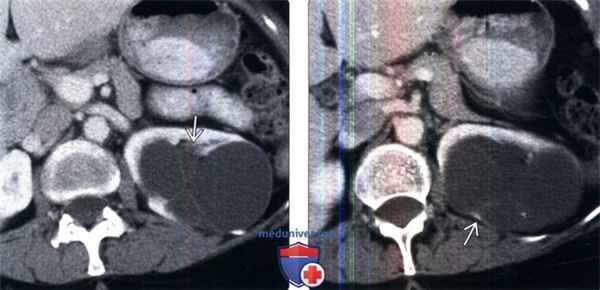

(Слева) MPT, Т2, режим подавления сигнала от жировой ткани, аксиальная проекция: высокая ИС от многокамерного кистозного образования, которое исходит из области верхнего полюса левой почки и продолжается прямо в почечный синус.

(Справа) МРТ, постконтрастное Т1, режим подавления сигнала от жировой ткани, аксиальная проекция: у того же пациента визуализирована тонкая перегородка мультилокулярного кистозного образования, накапливающая контраст.

(Слева) КТ с контрастированием, аксиальная проекция: классическая мультилокулярная кистозная нефрома в виде кистозного образования со множеством перегородок, выступающего в почечный синус. Почка функционирует нормально, отсутствуют васкулярная инвазия, лимфаденопатия и другие признаки злокачественности.

(Справа) КТ с контрастированием, аксиальная проекция: у этого же пациента выявлена классическая мультилокулярная кистозная нефрома в виде инкапсулированного поликистозного образования, выступающего в почечный синус.